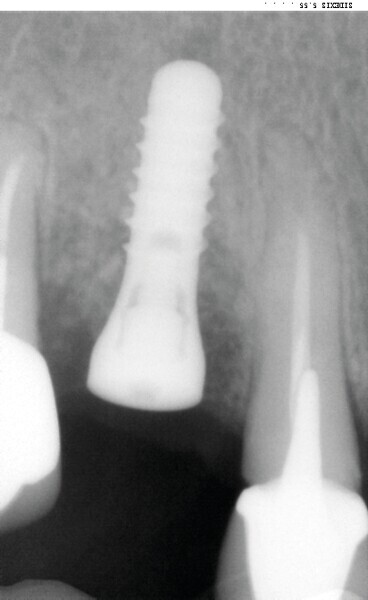

Dans certaines situations cliniques, l’étude radiologique tridimensionnelle montre un volume osseux exploitable en position de 18 ou 28. Il est alors aisé de réaliser le prélèvement au trépan, sur ces sites habituellement larges. Toute la pertinence dans ce cas est de le réaliser à travers la gencive kératinisée et obtenir ainsi une carotte ostéo-gingivale (Fig. 22). De ce fait, il ne faut pas faire d’incision ou de lambeau pour ouvrir l’accès au trépan. Le geste devient extrêmement rapide mais nécessite une bonne connaissance anatomique, une excellente analyse de la planification 3D, puis un bon repérage clinique.6

Pour connaître la profondeur de trépanation, il suffit d’enfoncer la sonde parodontale et de mesurer l’épaisseur de gencive sur l’os. En y ajoutant 4 mm, la profondeur finale est obtenue pour avoir suffisamment d’os. Une fois la carotte ostéogingivale prélevée (Figs. 23 et 24), il ne faut pas séparer l’os de la gencive, mais réduire l’épaisseur gingivale en supprimant la partie kératinisée (Fig. 25). Un implant cylindroconique (Straumann BLT 3,3 SLActive Roxolid) est parfaitement ancré (Fig. 26). La carotte d’os et sa gencive toujours adhérente, sont alors impactées transversalement à l’implant (Fig. 27). La partie osseuse spongieuse est au contact de l’implant, pendant que le conjonctif qui y est attaché, est utilisé comme un greffon conjonctif enfoui sous le lambeau vestibulaire.